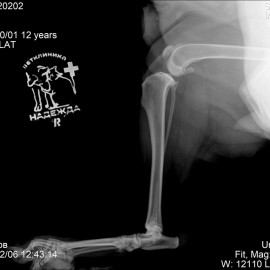

Пациент собака по кличке Линда возрастом 12 лет из города Вельск Архангельской области. Хозяин обратился с жалобой на хромоту на правую заднюю лапу. Проведены исследования, в ходе которых был поставлен диагноз: разрыв передней крестообразной связки правого коленного сустава. Проведена операция - TPLO.

Снимок 2 после операции.